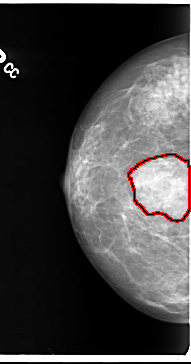

ics_version 1.0 filename B-3101-1 DATE_OF_STUDY 7 11 1996 PATIENT_AGE 48 FILM FILM_TYPE REGULAR DENSITY 3 DATE_DIGITIZED 6 2 1998 DIGITIZER LUMISYS LASER SEQUENCE LEFT_CC LINES 4632 PIXELS_PER_LINE 2632 BITS_PER_PIXEL 12 RESOLUTION 50 NON_OVERLAY LEFT_MLO LINES 4744 PIXELS_PER_LINE 2792 BITS_PER_PIXEL 12 RESOLUTION 50 NON_OVERLAY RIGHT_CC LINES 4720 PIXELS_PER_LINE 2472 BITS_PER_PIXEL 12 RESOLUTION 50 OVERLAY RIGHT_MLO LINES 4696 PIXELS_PER_LINE 2640 BITS_PER_PIXEL 12 RESOLUTION 50 OVERLAY |

FILE: B_3101_1.RIGHT_CC.OVERLAY TOTAL_ABNORMALITIES 1 ABNORMALITY 1 LESION_TYPE MASS SHAPE IRREGULAR-FOCAL_ASYMMETRIC_DENSITY MARGINS ILL_DEFINED ASSESSMENT 3 SUBTLETY 4 PATHOLOGY BENIGN TOTAL_OUTLINES 1 BOUNDARY |